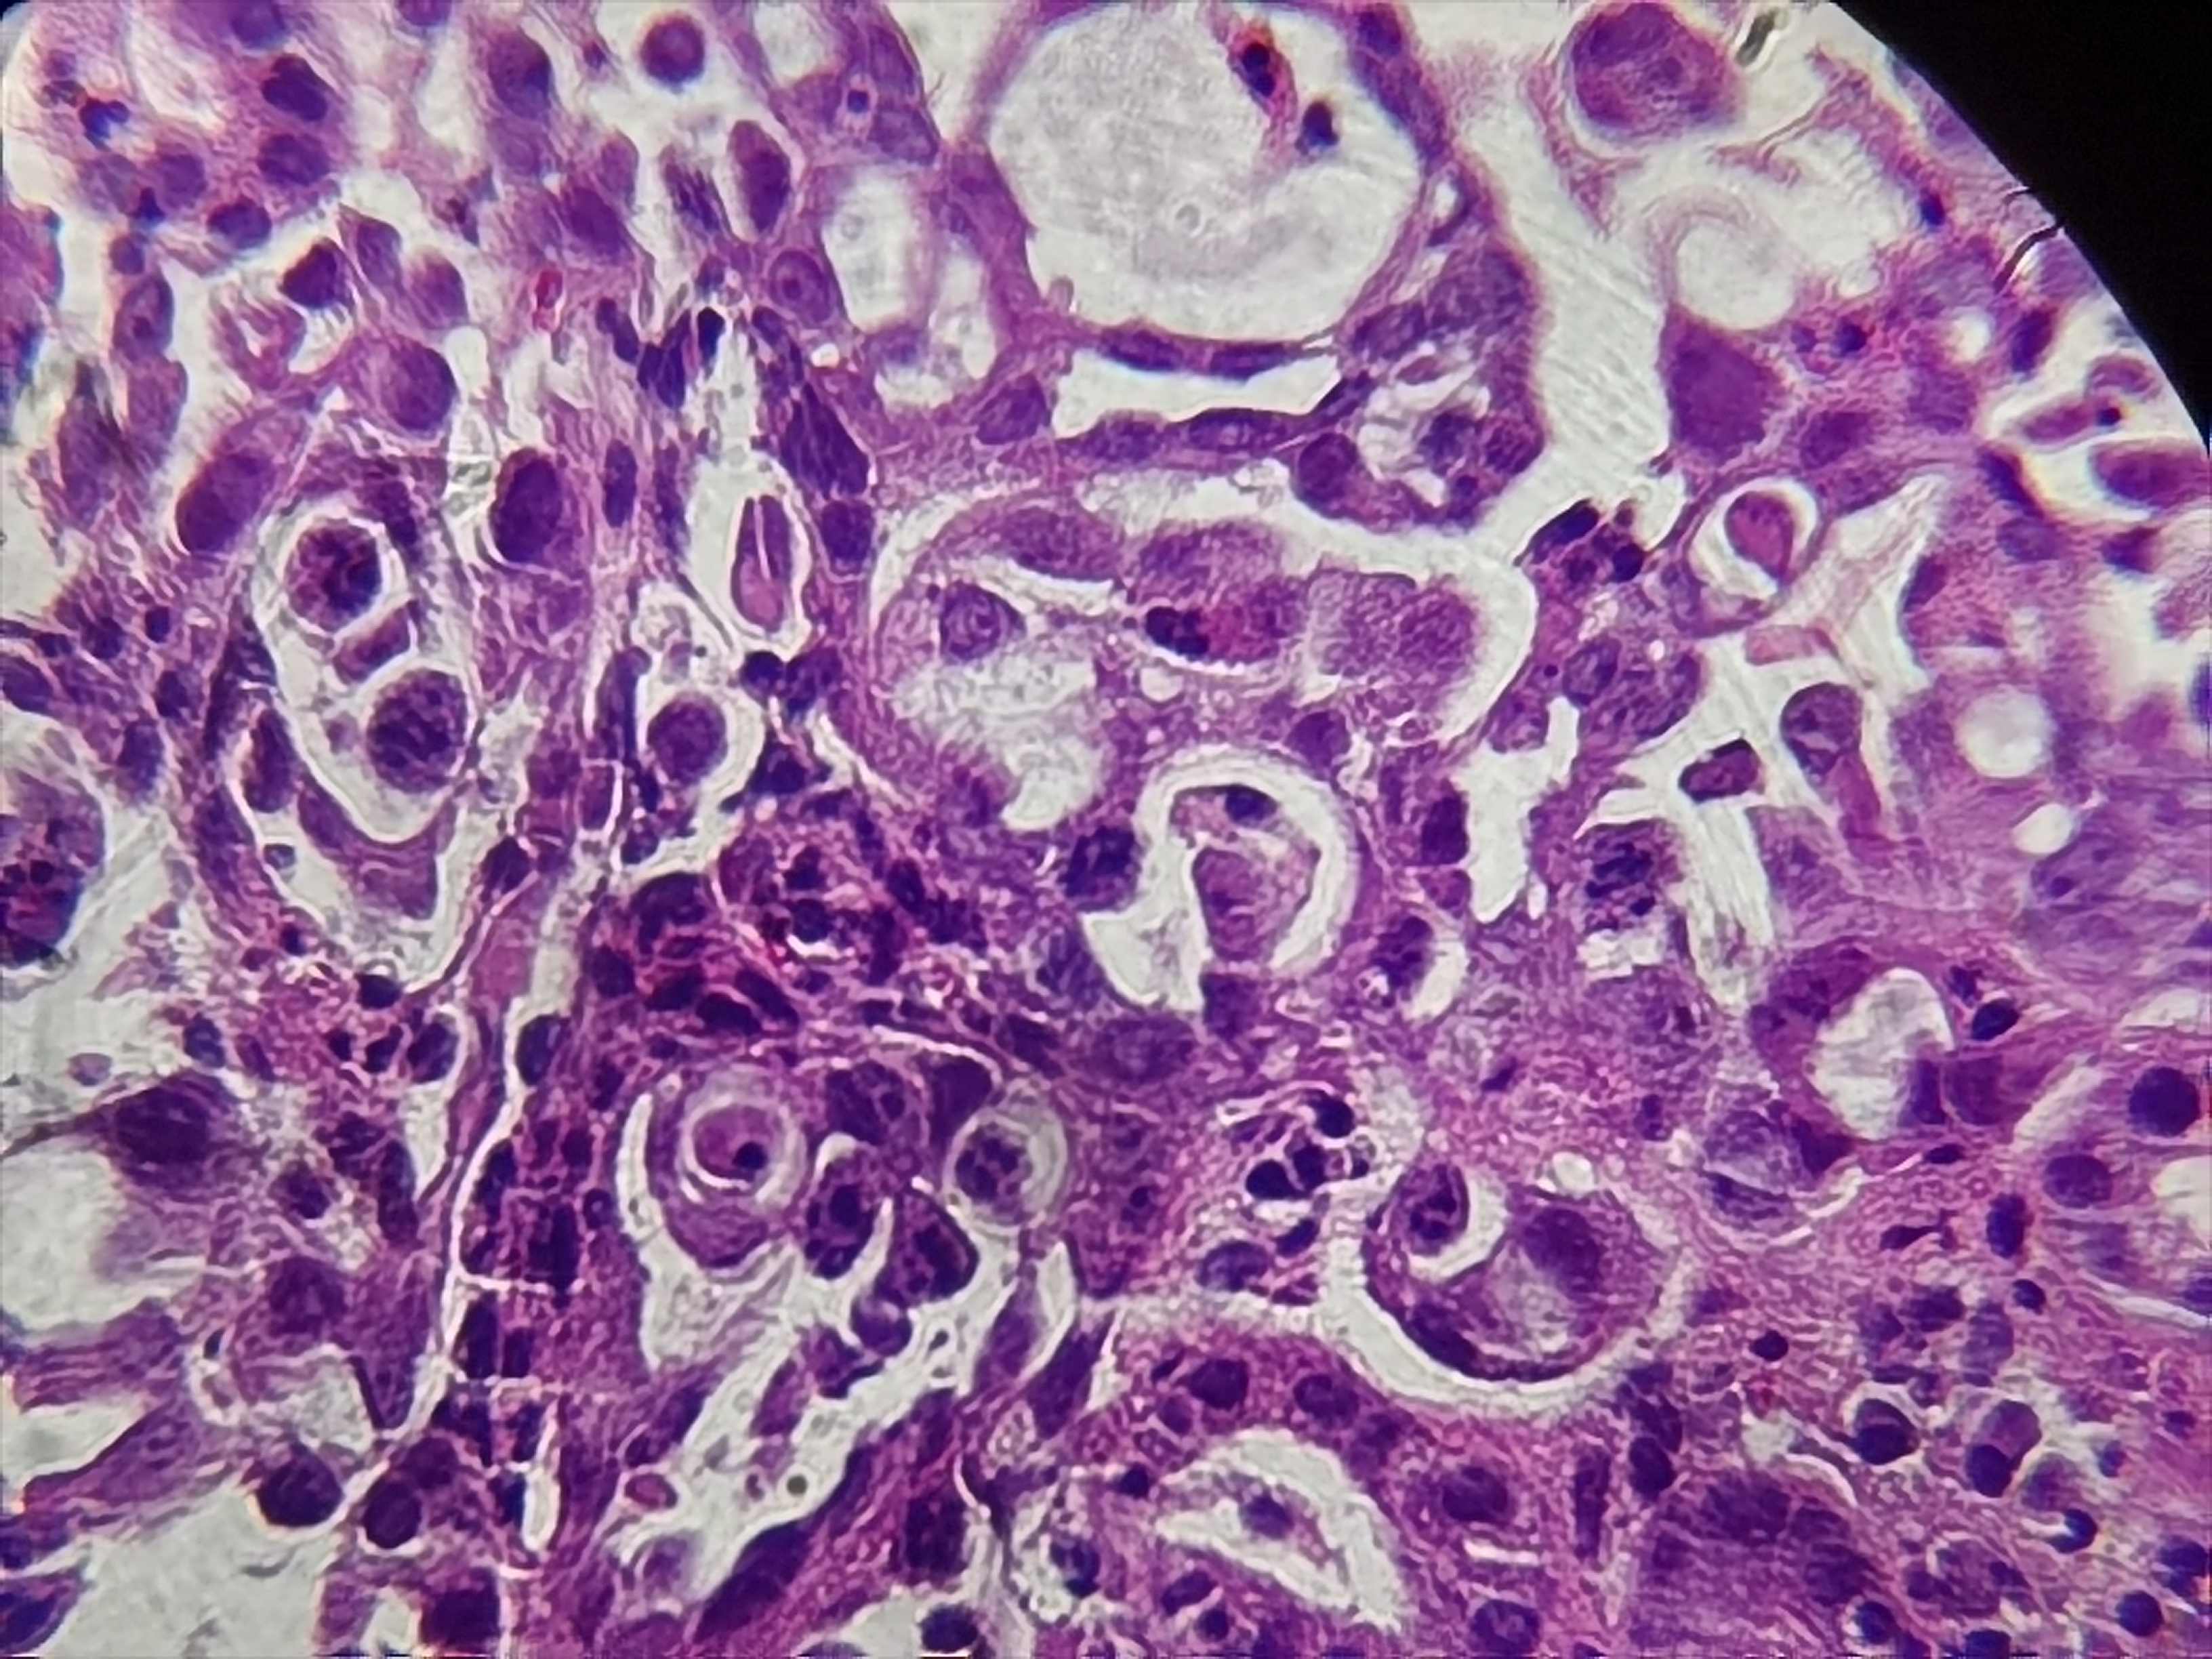

十二指肠球部活检

十二指肠球部可见一大小约0.5*0.6cm隆起性病变

标本名称

十二指肠球部粘膜活检

大体所见

灰白灰红组织1块

异位胰腺组织。